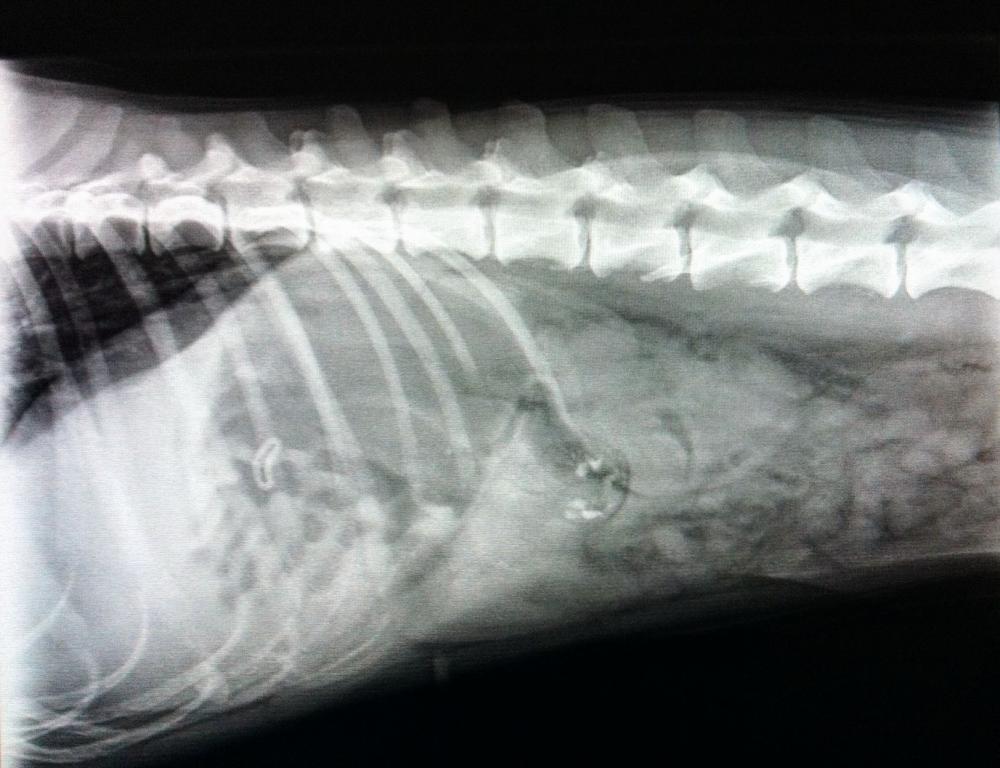

Sie wurde mit einer Schwäche der Hintergliedmaßen vom Haustierarzt ans Kleintierzentrum überwiesen. Nach Röntgen und Ultraschall stand fest, das die Schwäche nur sekundär zu einem Fremdkörper im Bauch des Hundes vorlag. Dieser war bereits vom Magen in den Dünndarm gewandert und verursachte einen Ileus (lebensbedrohlichen Darmverschluss). Aura's Blutwerte zeigten bereits einen massiven Flüssigkeitsverlust und erhöhte Entzündungszellen an, sodass es sich hier nicht um ein orthopädisches, sondern ein chirurgisches Problem handelte und sofort operiert werden musste.

Unser Chirurgen-Team staunte nicht schlecht, als sie ein Überraschungsei im Hundedarm vorfanden.. Durch einen kleinen Schnitt wurde der betroffene Darmabschnitt eröffnet und das Ü-Ei entfernt.